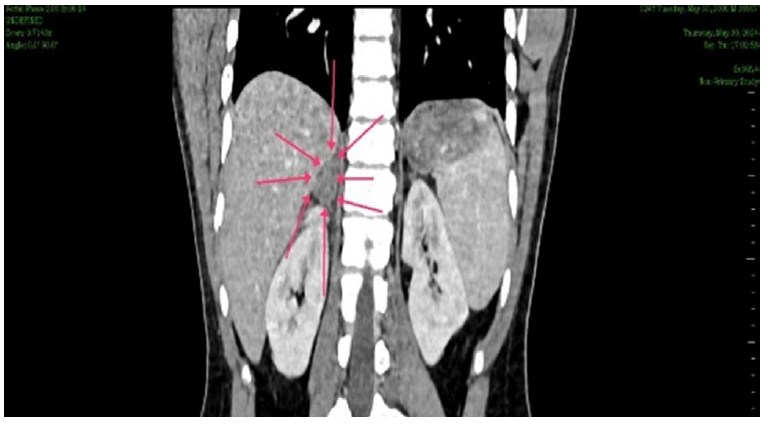

CT evaluation

CT scans were used to measure adrenal haematomas and classify them as irregular, oval, or circular. Other CT findings, including the enhanced area within the haematoma and associated injuries, were also evaluated (Figure 3 and 4).